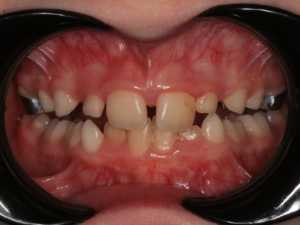

Лечение патологии прикуса у детей в период временного и сменного прикуса 3, 5 -10 лет

Неправильное положение нижней челюсти

Лучше лечение начинать в период молочного и переменного прикусов, когда половинки ещё полностью не срослись. Тогда шов ещё не окостенел. Поэтому лечение подобной конструкцией рекомендуется проводить до 18 лет. Максимальный возраст пациента не должен превышать 23 года.

- неверное соотношение обеих челюстей, когда верхняя челюсть уже нижней;

- верхний ряд зубных единиц выражается их скученностью;

- при выраженном перекрёстном прикусе;

- патологическое расположение клыков на верхней челюсти (когда клыкам не остаётся места для правильного расположения).

Аппарат Хааса один из немногих ортодонтических аппаратов , который позволяет достигнуть скелетного расширения в период активного роста ребёнка. Чем это обусловлено? Верхняя челюсть состоит из двух половин, которые связаны нёбным швом (хрящ). Именно он является зоной роста верхней челюсти. Воздействуя на эту зону : разрывая, растягивая её, стимулируется скелетное расширение. Но оно возможно до определённого возраста, пока шов не окостенеет. Поэтому данный ортодонтический аппарат используется в среднем от 5 до 12 лет.

В каких случаях показано применение аппарата Хааса?

1. Резкое сужение верхней челюсти

2. Большой дефицит места для постоянных зубов

Достаточно часто при лечении на аппарате Хааса мы наблюдаем положительные изменения и на нижней челюсти, хотя никаких конструкций для неё не использовали. Почему так происходит?

У детей в период активного роста очень хорошо проходит саморегуляция и когда нижняя челюсть высвобождается из «оков» маленькой и узкой верхней, она реализует свои потенциалы физиологического роста, расширяется, положение зубов улучшается.

Когда применяется аппарат Хааса? - самый оптимальный возраст для использования 6-8 лет. Однако данная конструкция применяется и в более позднем возрасте у детей и подростков, а так же у взрослых пациентов.

Показания к использованию ортодонтического аппарата Хааса:

- Скученное положение резцов

- Сужение верхней челюсти

- Готическое небо

- Двухсторонний перекрестный прикус